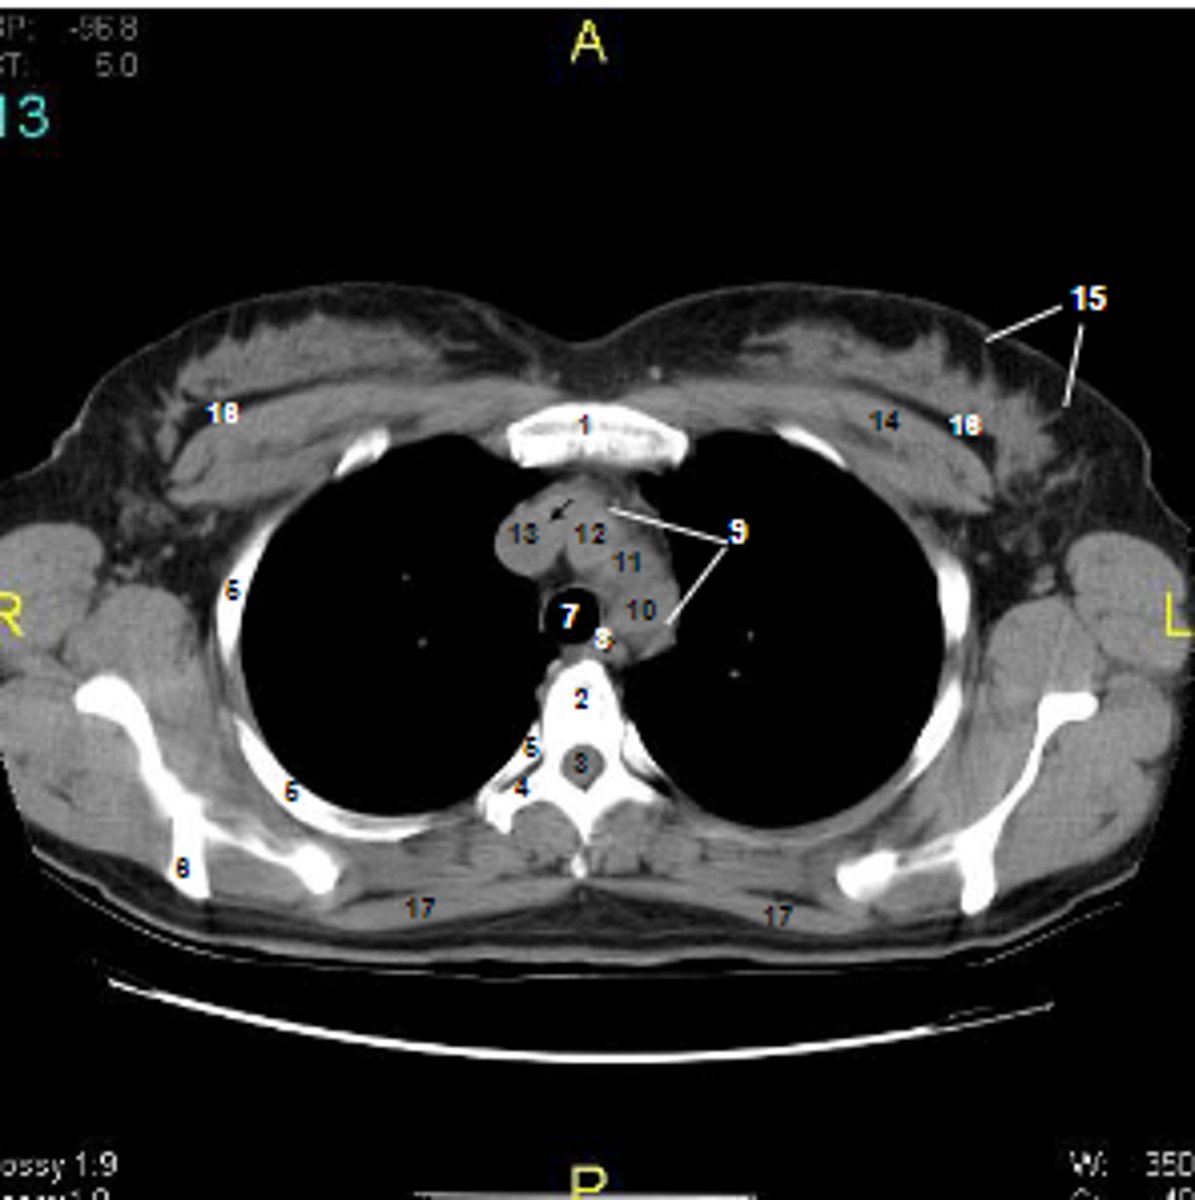

1

at what number is the sternum

2

at what number is the vertebral body

3

at what number is the vertebral canal/ spinal cord

4

at what number is the transverse process of vertebra

5

at what number is the rib

6

at what number is the spine of scapula

7

at what number is the trachea

8

at what number is the esophagus

9

at what number is the arch of aorta

10

at what number is the left subclavian artery

11

at what number is the common carotid artery

12

at what number is the brachiocephalic trunk

13

at what number is the superior vena cava

14

at what number is pectoralis major

15

at what number are Cooper's ligaments

16

at what number is the retromammary space

17

at what number is trapezius